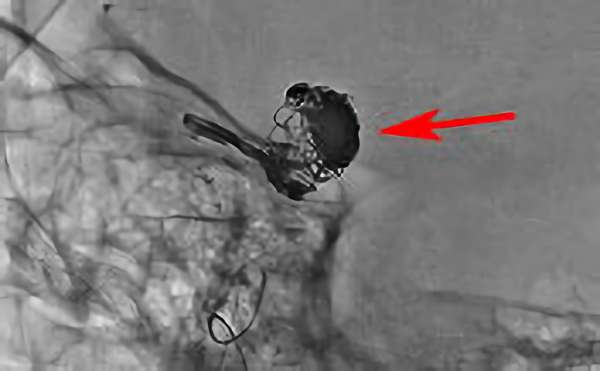

No.1631 手術前

No.1631 手術中

No.1631 手術後